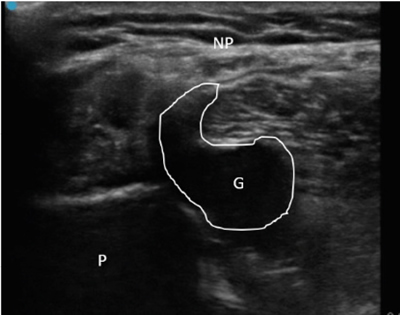

Neuropatía peronea secundaria a ganglión extraneural: revisión de literatura y propuesta de tratamiento. Caso no positivo

Peroneal neuropathy caused by an extraneural ganglion: literary review and treatment proposal. A non-positive case

Este artículo presenta el caso de un paciente de 69 años con una neuropatía compresiva peronea secundaria a un ganglión, inicialmente interpretada como una radiculopatía L5. Este incorrecto enfoque supuso la sobremedicación del paciente, un mal control algésico, la realización de una discectomía L4-L5 innecesaria y una pobre evolución neurológica.

Un enfoque diagnóstico correcto y un abordaje terapéutico precoz habrían supuesto una mayor mejoría clínica e incluso una recuperación neurológica completa del paciente. Por ello, este caso sirve para resaltar: a) el valor de la ecografía en neuropatías periféricas como herramienta diagnóstica y pronóstica y el de la ecografía en gangliones como arma diagnóstico-terapéutica; b) el uso de las pruebas diagnósticas como apoyo a una exploración física exhaustiva, y no como diagnóstico en sí mismas, y c) la importancia de la publicación de casos no positivos para optimizar recursos, evitar repetir errores, reducir el sesgo de publicación y facilitar el inicio de proyectos de investigación.

Figura 1

Figura 2